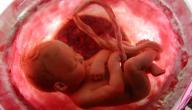

هو السائل الذي يسبح به الجنين في رحم الأم طيلة أربعين أسبوعًا، وهو فاعل رئيسي في نمو وتطور الجنين؛ فهو يعمل على امتصاص الصدمات والضربات التي تتعرض لها الحامل خصوصًا في منطقة البطن وجوانبه، ويقوم هذا السائل أيضًا بمثابة عازل يمنع انتقال العدوى من جسم الأم، وله دور في نمو الرئتين والجهاز التنفسي عند الجنين، كما وتتغير كمية هذا السائل خلال فترة الحمل لتصل لأعلى مستوى والبالغ 800-1000 مل عند 36-37 أسبوعًا من عُمر الحمل، وزيادة هذا السائل أو نقصانه يعد اختلالًا ويمثل نقص السائل ما نسبته 11% بين النساء الحوامل بينما اختلال زيادة هذا السائل تمثل نسبة 1% من أعداد الحوامل في معظم الإحصائيات، وسيتحدث هذا المقال عن أعراض نقص ماء الجنين في الشهر الثامن.[١]

هنالك عدد من الأعراض قد تبدو على الجنين المولود الذي عانى من حالة نقص السائل المحيط أثناء الحمل؛ فنقص السائل يجعل الكيس الذي يعيش فيه الجنين أضيق مما يُقيد الجنين ويعيق نموه وتطوره، بعض هذه الأعراض قد تكون ظاهرة في وجه الجنين مثل:[٢]